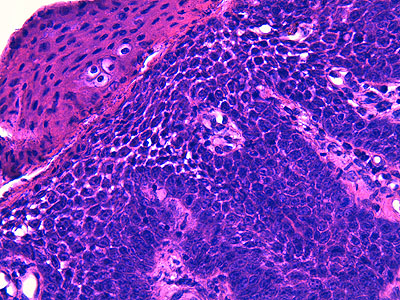

Photo 6 (Hémalun Eosine X 400) : vue rapprochée au fort grossissement d’une crête épithéliale

émanant de la gaine épithéliale externe d’un follicule pileux (portion infundibulaire).

L’aspect filiforme et longiligne s’accompagne d’une certaine perte de polarité des cellules basales

dont le grand axe cytoplasmique devient parallèle au grand axe de la crête épithéliale, au lieu

d’être perpendiculaire. La couche la plus basale perd ainsi son habituel aspect palissadique.

Légendes de la Photo 6 :

- Triangles bleus clairs : contours de crêtes épithéliales allongées, filiformes, ramifiées et branchues, peuplées de cellules basales hyperbasophiles, émanant de la gaine épithéliale externe des infundibula folliculaires

- Flèches rouge : parakératose folliculaire

- Étoiles rouge pleines : Le derme est faiblement à modérément inflammatoire (infiltrat mononucléé)

- Étoiles rouges claires : angiectasie des capillaires sanguins

- Ronds marron :tiges pilaires

- Flèches orange : mélanocytes

- Flèches jaune : mélanophages